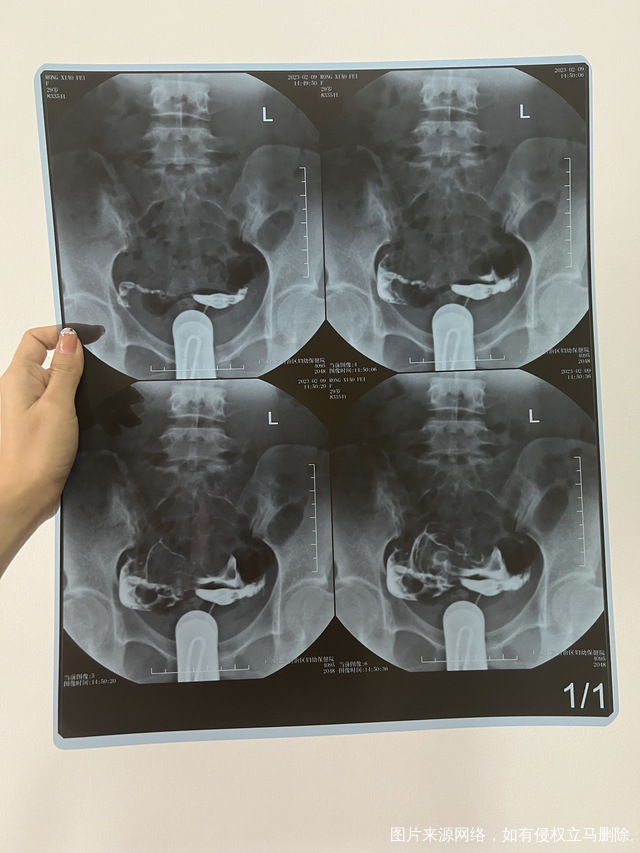

输卵管是否通畅为什么还怀不上